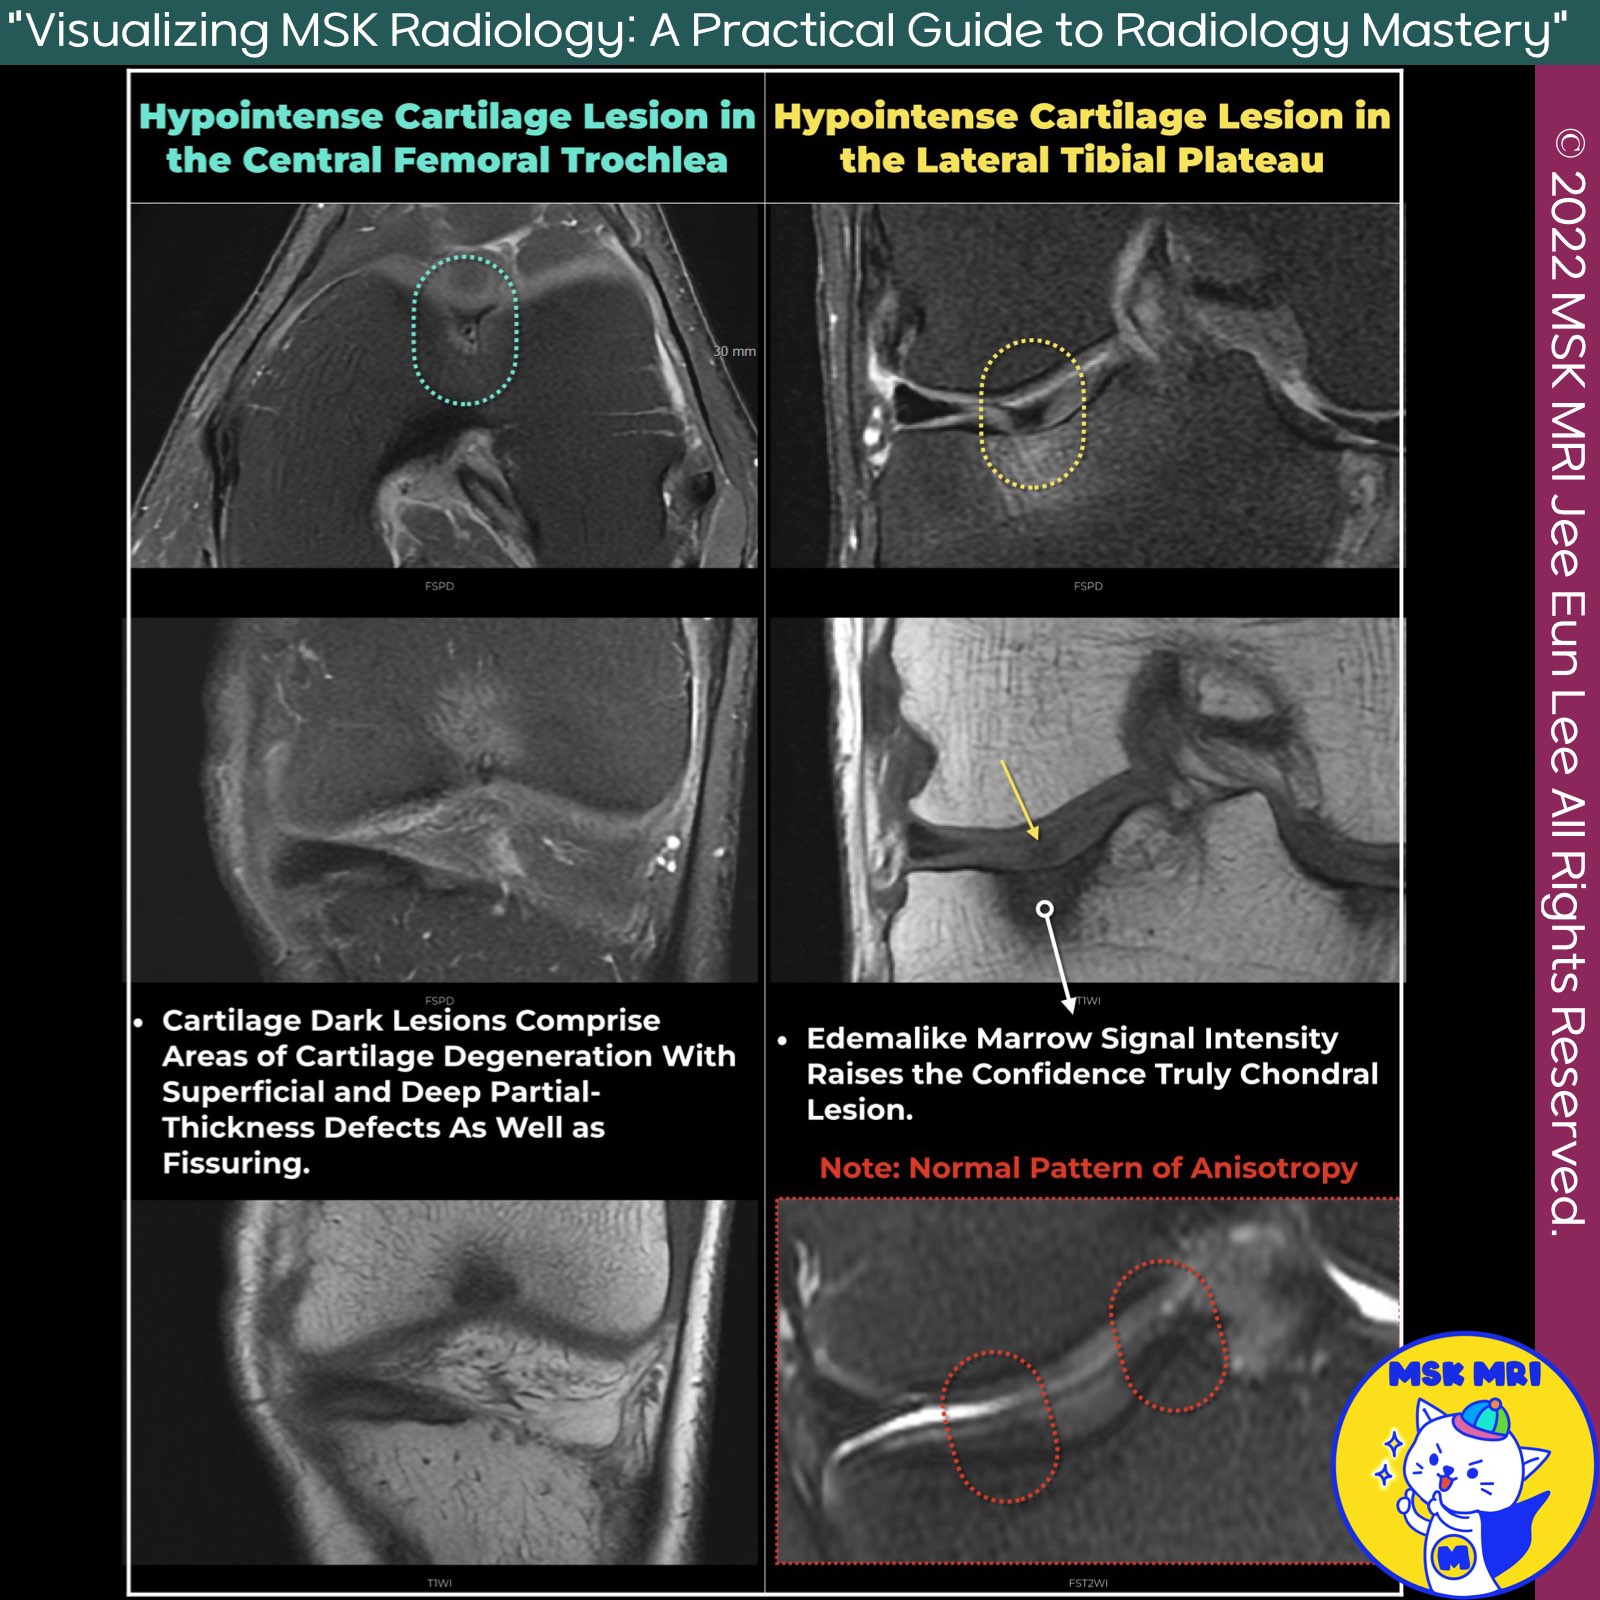

📌Hypointense Lesion in Cartilage

- Hypointense lesions in cartilage, known as cartilage dark lesions, are focal areas seen as low signal intensity on MRI.

- They are significant indicators of cartilage degeneration, often observed during knee arthroscopy.

- Morphologically Normal Cartilage: These lesions have a 64% positive predictive value for degeneration detection at knee arthroscopy.

- Location and Appearance: Typically found in the middle zone, they can be linear or globular and are commonly associated with fibrillation or fissuring.

- Common Sites: Most commonly involve the femoral trochlea, lateral femoral condyle, and retropatellar areas.

- Arthroscopic Findings: Cartilage Degeneration: Represents areas with superficial and deep partial-thickness defects and fissuring.

- Proteoglycan Concentration: Lesions are softer due to lower proteoglycan concentration and water content, seen in the central aspect of the trochlea.

- Chondrocalcinosis: Calcium pyrophosphate deposition may cause scattered, punctate, hypointense signal foci, best detected with gradient-echo MRI sequences.

- Tissue Anisotropy Disruption: Caused by increased exposure of "bound" protons on disrupted collagen to bulk water or mature fibrocartilage.

- Magic Angle Effect: Focal cartilage degeneration leads to losing the magic angle effect and more rapid T2 decay due to altered collagen fiber orientation.

- Distinguishing from Normal Anisotropy: Radiologists must distinguish these areas from normal anisotropy patterns.